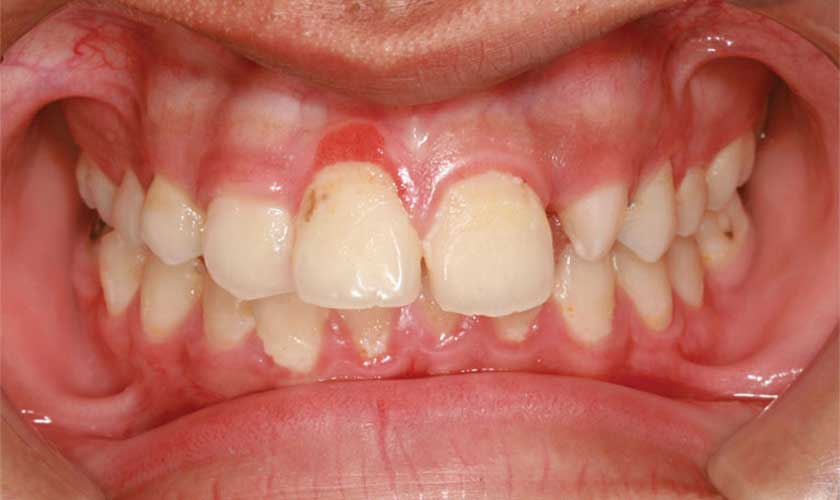

Viêm nướu răng cửa là tình trạng nướu răng cửa bị kích ứng, đỏ và sưng (viêm) nướu, Điều quan trọng là tiến hành thăm khám và điều trị kịp thời để tránh trường hợp bệnh viêm nướu răng tiến triển nghiêm trọng hơn dẫn đến viêm nha chu và mất răng.

Viêm nướu răng cửa

Theo thời gian, nướu bị viêm sẽ bị sưng và dễ chảy máu. Sâu răng (sâu răng) cũng có thể xảy ra. Nếu không được điều trị, viêm nướu có thể tiến triển thành viêm nha chu và cuối cùng là mất răng.